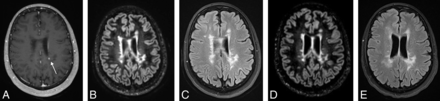

Progression of Lesions across Time

Seventy-six MRIs had a prior comparison in our study period, with a median interval of 236 days (interquartile range, 191–367 days) between examinations. Of these, a total of 17 (22%) had imaging evidence of progression, defined as new lesions (either on DIR/FLAIR or enhancing) compared with the most immediate prior MR imaging examination (Table 2). The presence of enhancing lesions was associated with new lesions on DIR and FLAIR (P < .001). Only one of these MR imaging examinations had a new lesion that was only detectable on postcontrast imaging as a single enhancing lesion in a region of confluent white matter abnormality that did not show interval change on DIR and FLAIR (Fig 2), because the lesion could not be differentiated from confluent periventricular white matter signal abnormality on DIR or FLAIR. Thus, 16 of 17 cases of progression could be detected on the basis of new DIR or FLAIR lesions alone (sensitivity, 94%).

3D contrast-enhanced T1 MPRAGE (A) demonstrating a left periventricular enhancing lesion (arrow) in a region of confluent white matter lesions that is not detectable as new between the more recent 3D-DIR (B) and 2D-FLAIR (C) and prior 3D-DIR (D) and 2D-FLAIR (E).